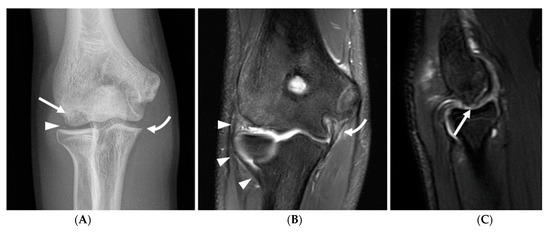

Figure 6.

A 19-year-old male collegiate right-hand-dominant baseball pitcher with mechanical symptoms in the right elbow for 2–3 years and an inability to extend elbow. (A) Axial T1-weighted image demonstrates joint space narrowing in the posterior humeroulnar joint, with prominent subchondral sclerosis and small marginal osteophytes (arrows). (B) Sagittal fat-saturated T2-weighted image demonstrates multiple joint bodies in the olecranon fossa (curved arrow) and fragmentation of the olecranon tip (arrow). (C) Coronal fat-saturated T2-weighted image demonstrates marked thickening of the anterior band of the ulnar collateral ligament (arrow). Joint bodies are again seen in the olecranon fossa (curved arrow). (D) Arthroscopic image demonstrating hypertrophy of the olecranon process (asterisk) and multiple joint bodies (curved arrow). (E) Photograph showing the multiple joint bodies retrieved at surgery.

Olecranon apophysitis was also only seen in athletes in subgroup 1 (Figure 5), with the exception of one athlete in subgroup 3 who had a chronic injury with associated nonunion of the olecranon apophysis, and olecranon stress reaction or fractures were observed with a higher frequency in subgroups 1 and 2 (12% and 24%, respectively), with a chronic injury seen in a single subject in subgroup 3. Other findings consistent with repetitive loading secondary to posteromedial shear and resultant degenerative changes in the posterior humeroulnar joint were observed with high frequency across all age groups, although this progressively increased with age. Specifically, humeroulnar osteophytes were observed in 62% of subjects in subgroup 1, 72% of subjects in subgroup 2, and 74% of subjects in subgroup 3 (Figure 6). This is in contrast to controls, where only 17% of subjects demonstrated posterior humeroulnar osteophytes.

Although grade 1 UCL injuries occurred with similar frequency across age groups, grade 3 UCL injuries were only seen in athletes in subgroup 3. Similarly, grade 2 UCL injuries occurred with greater frequency in older athletes (48% of subjects in subgroup 2 and 49% in subgroup 3, compared to 23% in subgroup 1). No evidence of UCL injury was observed in control subjects. Flexor–pronator, common extensor, triceps, and biceps/brachialis tendinopathy and injury demonstrated a similar pattern with the greatest frequency observed in athletes in subgroup 3.